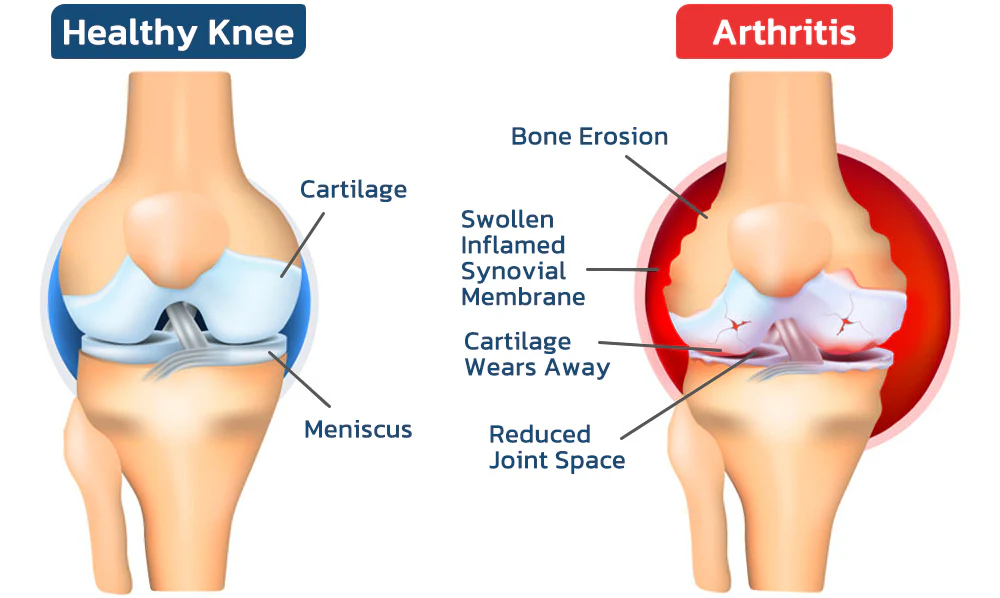

The dangers of arthritis?

According to estimates by the World Health Organization (WHO), approximately 300 million people worldwide suffer from arthritis. Less severe cases include arthritis, rheumatism and gout, with symptoms including pain, stiffness, swelling, difficulty with movement, fatigue and loss of range of motion. Severe cases can lead to joint deformities, fever and severe joint pain, resulting in long-term pain and disability. In extreme cases, orthopedic conditions can even lead to life-threatening complications.

Common Orthopedic Joint Symptoms

Arthritis refers to inflammatory diseases that occur in the joints and surrounding tissues of the human body and are caused by inflammation, infection, degeneration, trauma, or other factors. They can be divided into dozens of types. Clinical manifestations include redness, swelling, heat, pain, dysfunction, and deformity of joints, which can lead to joint disability and affect the quality of life of patients.

According to statistics, osteoarthritis affects half of the population over the age of 50 in the United States and 90% of women and 80% of men over the age of 65. The life expectancy of those with severe symptoms is shortened by about 10 to 15 years.

Gout (metabolic arthritis) is caused by an increase in glancing biosynthesis, excessive production of uric acid, or poor excretion of uric acid, resulting in an increase in uric acid in the blood and thus causing gout, which is characterized by hyperuricemia and recurrent episodes of gouty acute arthritis, commonly occurring in the joints of the big toe but also in the hands, knees, elbows, etc.